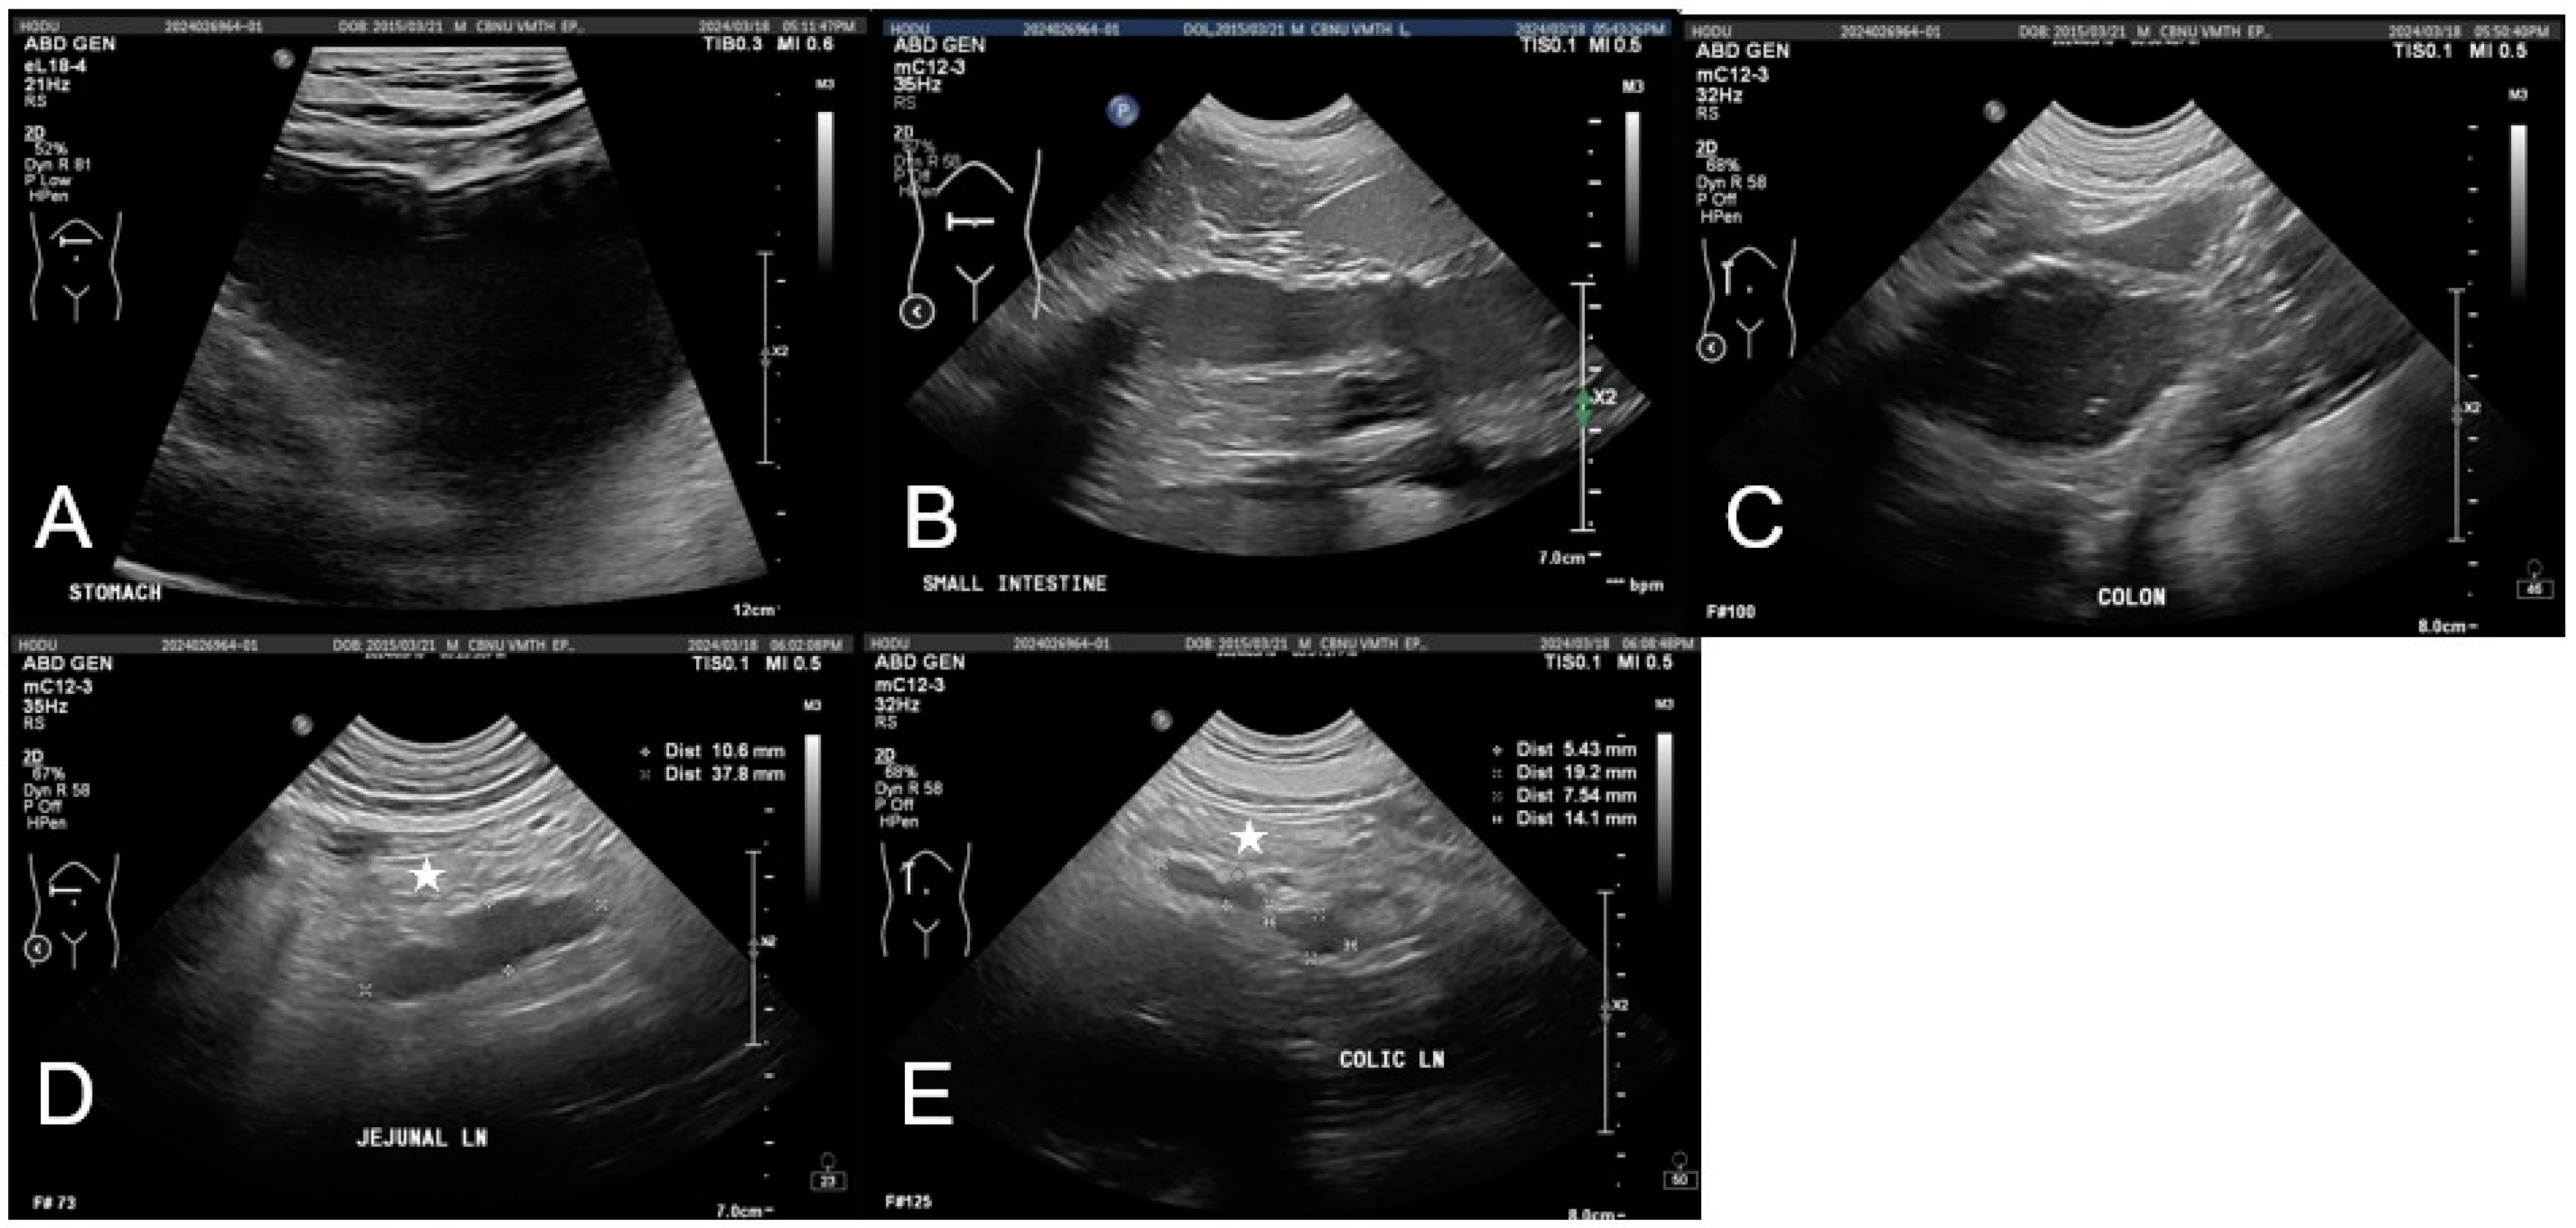

Abdominal imaging indicated gastrointestinal dysfunction. Radiographs showed mild gastric distension and a fluid-filled small intestine without evidence of mechanical obstruction. Ultrasonography revealed gastrointestinal dilation, fluid retention, and hypomotility, suggestive of functional ileus with mild peritoneal edema and mesenteric lymphadenopathy (Figure 2). No significant abnormalities were observed in the hepatobiliary system, including liver size, echotexture, and gallbladder structure, aside from mild echogenic sludge without gallbladder wall thickening or bile duct dilation.

Figure 2.

The imaging findings of gastrointestinal complications following ingestion of potting soil in a dog. (A) The stomach contains a significant accumulation of anechoic fluid with mild echogenic material, leading to distension. (B,C) Marked dilation of the small (B) and large (C) intestines with decreased peristalsis and fluid accumulation observed. (D,E) Jejunal lymph nodes and colic lymph nodes are mildly enlarged and appear hypoechoic. The peritoneum in the right mid-abdominal region (star) appears mildly hyperechoic and edematous.